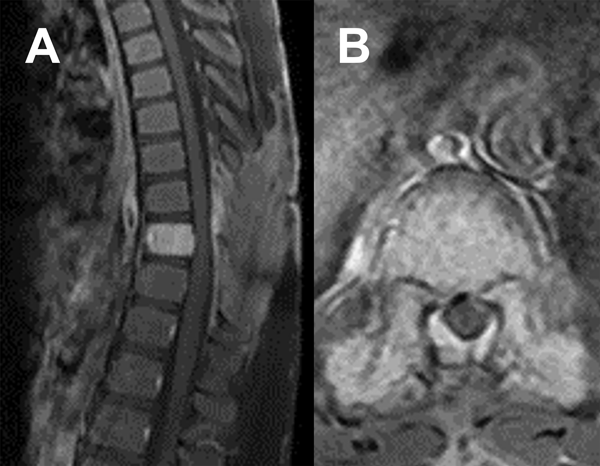

Durante el procedimiento se realizó laminectomía D8 y D9 con exéresis del componente epidural. Durante la cirugía, la lesión fue muy hemorrágica, lo que dificultó la hemostasia. La evolución inicial fue favorable con recuperación progresiva del déficit neurológico. En el cuarto día postoperatorio presentó nuevo deterioro motor. La RM (Figura 3) mostró un hematoma compresivo en el lecho quirúrgico. Se indicó nueva cirugía de evacuación. El paciente logró mejoría continua y progresiva de su déficit.

Figura 3. RM postquirúrgica inmediata. A) Secuencia T2 sagital. B) Secuencia T2 axial.

Las imágenes de resonancia magnética (RM) pueden anticipar las características del hemangioma a tratar. Habitualmente, los HV son hiperintensos tanto en T1 como en T2. Sin embargo, cuando son activos, agresivos o invasivos (Enneking III), suelen ser isointensos en T1 e hiperintensos en T2 (ver Figura 2). Según Daniel Eichberg, la embolización tumoral puede realizarse de forma prequirúrgica para facilitar la cirugía. Algunos autores informan que este procedimiento puede ser un tratamiento único con respuestas curativas, sin embargo, otros describen una respuesta meramente temporal o nula en HV grados III sin cirugía postembolización ni radioterapia.3 Finalmente, la radioterapia, como afirma Keaton Piper, puede usarse como monoterapia para el dolor o como complemento de la cirugía, demostrando una disminución de la recidiva a los 2 años en resecciones subtotales de un 7 a un 30%.5